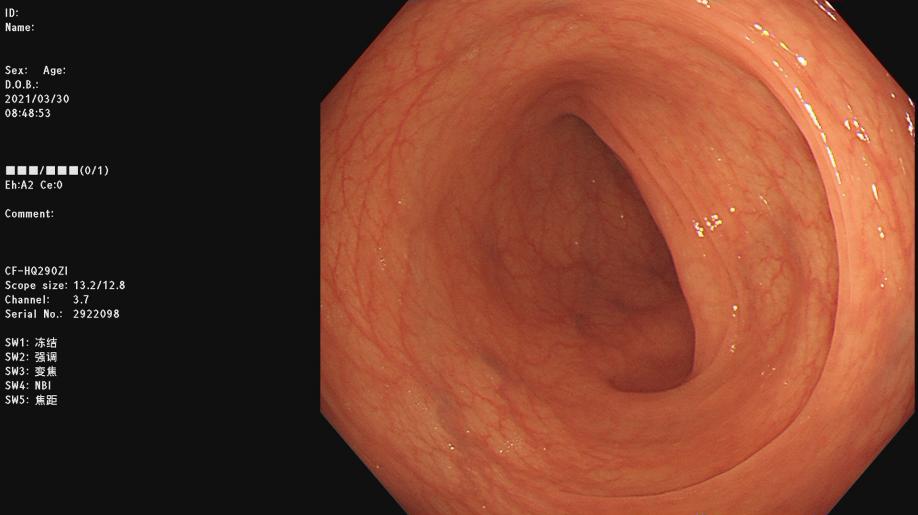

镜下肠道示意图:

肠道准备合格

镜下观察良好